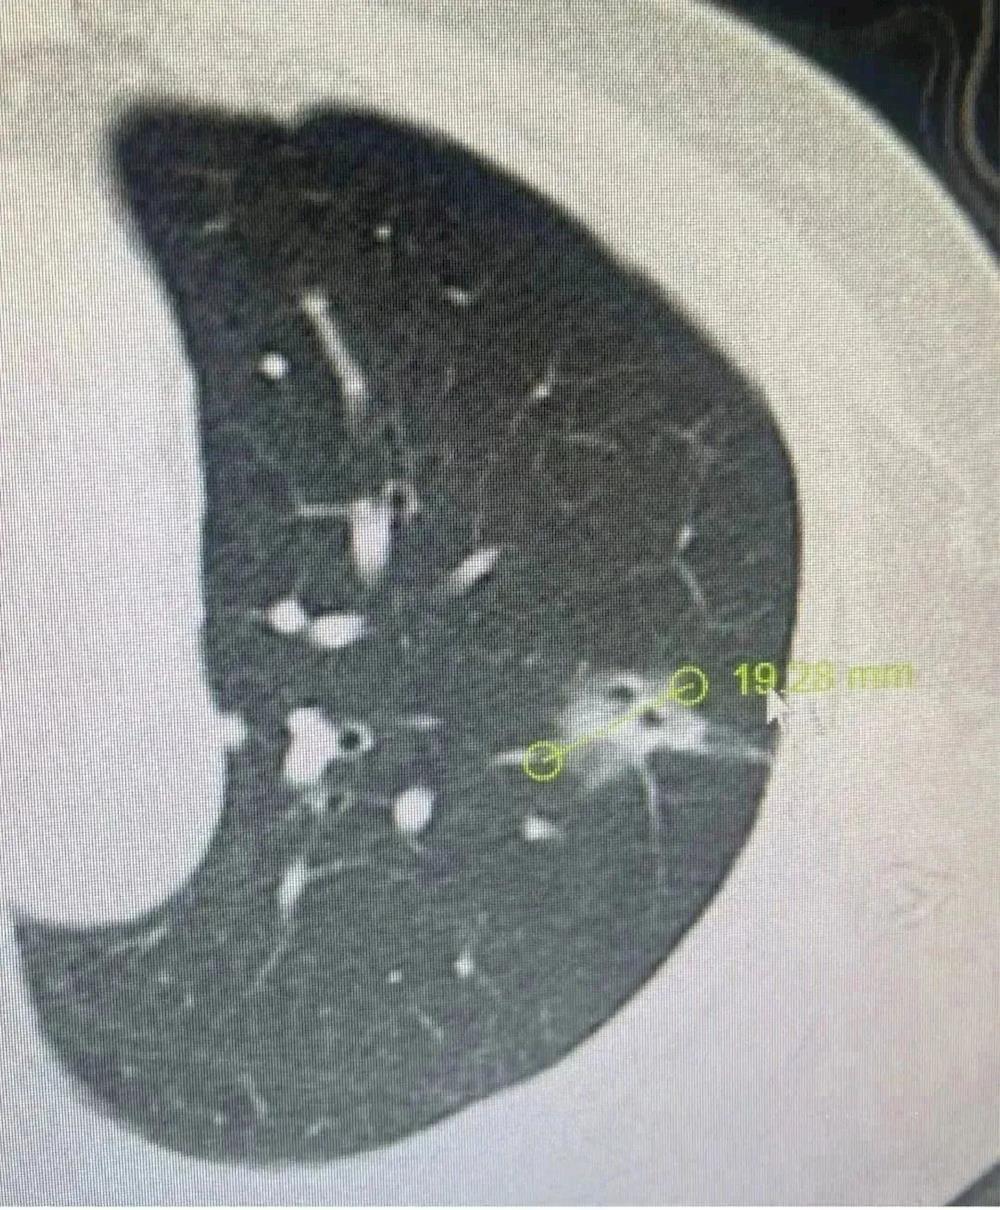

邓奶奶在去年年底CT检查时发现肺部有一个长径接近2cm的毛玻璃结节,当时因为处于疫情防控期间,医生建议患者观察一段时间后复查。

患者左上肺上的混合毛玻璃结节